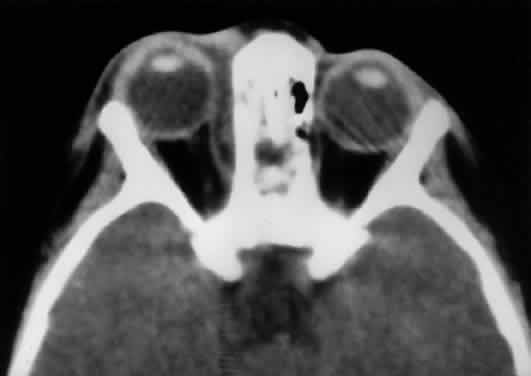

Second, the motor fibers to the EOMs usually enter the inner aspect of each muscle at the junction of the posterior one third and the anterior two thirds of the muscle's length. The exception is the nerve to the inferior oblique, which runs along the lateral aspect of the inferior rectus muscle to enter the inferior oblique muscle near the globe's equator (see Fig. 14). This nerve may be damaged with manipulation of inferior orbital soft tissue during repair of an orbital floor fracture. Because the parasympathetic fibers of the pupil also travel with the nerve to the inferior oblique at the orbital apex, any anterior traction may cause contusion to these more posterior fibers, resulting in a postoperative Adie's pupil.14 VASCULAR SUPPLY Arteries The tissues of the orbit and periorbital region derive their blood supply from two sources—the internal and external carotid arteries.15 Although the majority of orbital blood supply comes from the ICA, anastomoses with external carotid supply are numerous. The ICA enters the calvarium through the foramen lacerum, runs near the posterior clinoid process, and then makes a sharp turn to enter the CS with the abducens nerve (see Fig. 13). As already noted, within the CS the ICA has an S-shaped course called the carotid siphon. As the ICA exits the CS, it gives off its first major intracranial branch, the ophthalmic artery. Before giving off the ophthalmic artery, the ICA has several minor branches that supply the meninges, including the dura of the lateral wall of the CS. An abnormal communication between the arterial and venous supply of the CS results in either a carotid-cavernous fistula or a dural-sinus fistula (Fig. 18A). Because of the larger caliber of the ICA, a carotid-cavernous fistula is usually symptomatic secondary to a high flow state, possibly manifesting as orbital/ocular ischemia and increased intraocular pressure. This type of fistula is most commonly encountered in younger patients after blunt trauma and may require invasive neuroradiologic treatment (Fig. 18B). Conversely, a dural-sinus fistula is typically a low-flow state because the abnormal communication forms between the small-caliber dural arterial feeders of the lateral CS wall and the venous plexus of the CS. Such fistulas are usually seen in older individuals as a spontaneous event. Depending on the severity of symptoms, most dural sinus fistulas are simply followed by observation because of the high rate of spontaneous closure. The ophthalmic artery enters the optic canal inferolateral to the optic nerve, carrying with it a sympathetic plexus from the ICA. The intraorbital course of the ophthalmic artery is highly variable. In about 83% of cases, the artery crosses over the optic canal from lateral to medial and continues to travel superomedially in the orbit to its terminal branches. While still within the orbit, the ophthalmic artery gives off several branches.16 These are most easily subdivided into three groups: ocular, muscular, and extraorbital (Table 12, Fig. 19).